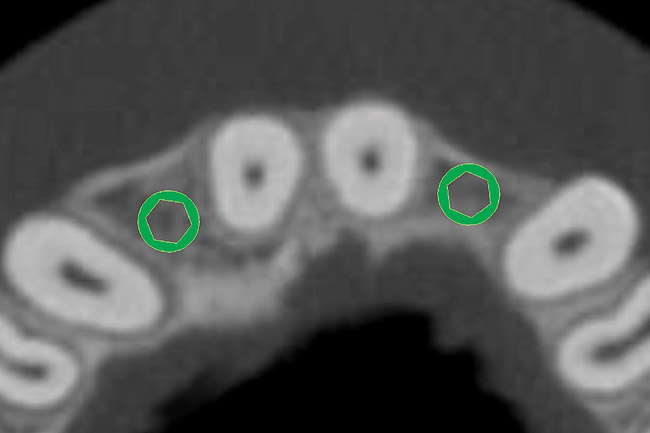

The CT axial views represent an important instrument in gaining a better understanding of anatomical features that cannot be determined by any other imaging modality (Figure 10). When the maxilla is sliced axially at the level where the roots meet the crest of the bone, the adjacent and surrounding root morphology can be revealed. Of note are the individual and different shapes of each of the central incisors, canines, premolars, and molar roots. These images reflect a phenomenon defined by the author as the “restorative dilemma.” Clinicians encounter this often difficult dilemma when attempting to re-establish morphologically correct emergence profiles in prosthetic teeth as they ascend from the round shape of the implant(s). When planning for the placement of the implant in the left lateral incisor area, there appeared to be adequate mesial-distal space between roots as seen in the axial view of Figure 11. A closer inspection of the planned site for the right lateral incisor revealed a more narrow space, further complicated by the distal rotation of the palatal aspect of the tooth root. Based on this preliminary position, the 3.75-mm diameter, straight-walled implant can be seen encroaching on the lamina dura periodontal ligament space of the right canine and central incisor. If there was not adequate room for this diameter and type of implant, the adjacent teeth could sustain potential iatrogenic damage. Therefore, additional “tweaking” of the virtual placement was necessary to diminish this risk.

Figure 10  SOFTWARE IMAGING By slicing the maxilla axially, the images revealed the differing morphology of the central incisors, canines, premolar, and molar roots.

Figure 10

Figure 11  SOFTWARE IMAGING  The left simulated implant can be seen encroaching on the adjacent lamina dura.

Figure 11